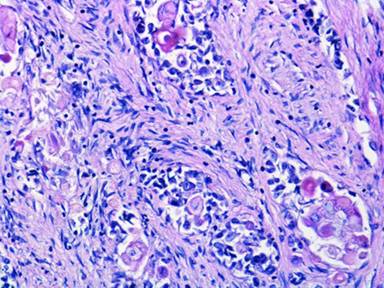

Autopsy showed the immediate cause of death was a 2 cm right main pulmonary artery embolus leading to acute cardiopulmonary compromise. Significant findings on autopsy included multiple metastatic nodules in the liver and lungs and a solitary 3.6 cm yellow ill-defined firm primary tumor in the body of the pancreas. Tumor was also discovered in random samples of breast tissue by microscopy. Histologically, the tumor was composed of nests of bland squamous cells surrounded by aggregates of primitive-appearing cells divided by hypercellular stroma. The squamous cells had a pilomatricoma-like appearance with abundant pink cytoplasm, small nuclei, frequent anucleation, and well defined polygonal cell borders (Figure 1). A focal giant cell reaction was present in some areas. The primitive appearing cells had moderately coarse chromatin and scant cytoplasm. In addition, a substantial component of the tumor in the liver showed ductal differentiation transitioning with the squamous component. Immunohistochemistry revealed that the tumor stained positive for cytokeratin AE1/AE3, CAM 5.2, CK5/6, and focally positive for CK7, CA 125, CEA, CA 19-9. The primitive appearing tumor cells exhibited neuroendocrine features with strong staining for CD56 and focal staining for synaptophysin. The tumor was negative for CK20, p63, trypsin, chymotrypsin, lipase, S100, chromogranin, AFP, TTF-1, SP-A, ER, PR, mammaglobin, CDX2, WT-1, and GCDFP-15. Ki-67 proliferative-index stained 5-10% of the tumor cells. The pathological diagnosis was pancreatoblastoma.

Figure 1. Primary pancreatic tumor consisting of squamous nests surrounded by primitive appearing cells with moderately coarse chromatin and scant cytoplasm. Notably, the squamous cells have abundant pink cytoplasm and frequent anucleation. The tumor is contained within a background of hypercellular stroma (hematoxylin-eosin, original magnification x200). |